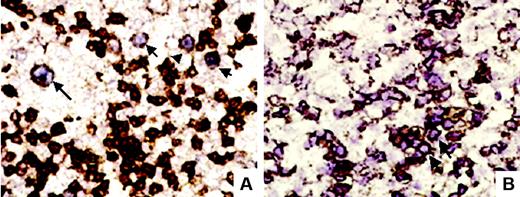

A semiquantitative, visual method was used to quantify the positivity of EBER-ISH. EBER-ISH–positive cases were classified into 4 categories (Figure 1A): Cases quoted as 1 showed only rare, less than 1% scattered positive cells; those quoted as 2 showing obvious, although scattered (1% to 5%) positive cells; those quoted as 3 showing numerous (5% to 50%) positive cells; and those quoted as 4 showing homogeneous positivity in more than 50% of cells.

Estimation of EBER expression level with spline curve. (A) Four-level semiquantitative estimation of different levels of EBER expression, quoted from 0 (EBER-ISH negative) to 4. Examples are shown at original magnification ×100 (top row) and ×200 (bottom row). Images were captured with a Zeiss Axioskop2 microscope (Zeiss, Oberkochen, Germany) and Neofluar 100×/0.1 NA optical lenses (Zeiss). Photographs were taken with a DP70 Olympus camera (Olympus, Tokyo, Japan). Image acquisition was performed with Olympus DP Controller 2002, and images were processed with Adobe Photoshop v7.0 (Adobe Systems, San Jose, CA). (B) The spline curve shows how the relative risk of death changes with the level of EBER positivity. The dotted lines show the 95% confidence interval. Bold lines show the best cut-off point.

EBER-ISH was positive at any level in 45 (41%) of 110 analyzed samples. According to the 4-level semiquantitative estimation illustrated in Figure 1A, 16 (14%) of 110 were quoted as 1; 17 (15%) of 110, as 2; 10 (9%) of 110, as 3; and only 2 (1.8%) of 110, as 4. As shown by the variation of the spline curve (Figure 1B), the best threshold lies between no expression (0) and level 1 expression. It is above this threshold that the spline curve crosses the 0 line, thus indicating a negative impact on survival. Thus, the following results separate only negative (0) and positive (1-4) cases.

Double-labeling techniques. (A) EBER-ISH and CD20 double-labeling showed in this case large CD20+ B cells (arrows) showing a purplish nuclear staining corresponding to EBERs (original magnification ×400). (B) In another case, EBER-ISH and CD2 double-labeling showed clusters (arrow) of CD2 and EBER-ISH–positive cells (original magnification ×400).